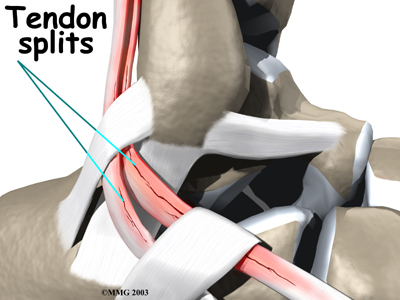

Over time, the tendon thickens as scar tissue tries to repair the damaged tendon. The area of tendonosis in the tendon is weaker than normal tendon. The weakened, degenerative tendon may tear. This usually causes a lengthwise in the peroneal tendons rather than a rupture. These splits or tears are most common in the peroneus brevis tendon, probably because it lies in front of the peroneus longus. It is more vulnerable to friction because it rubs against the groove in the fibula bone.

Tendon Repair

Tendonosis may require repair if a preoneal tendon is split down its length. This type of tear mainly affects the peroneus brevis. The surgeon fixes this problem by first around the tendons. If the split is smaller than one-third the width of the tendon, the torn portion may simply be removed. Larger splits are sutured along the length of the tendon. The tendon sheath is , and the skin is closed with sutures.